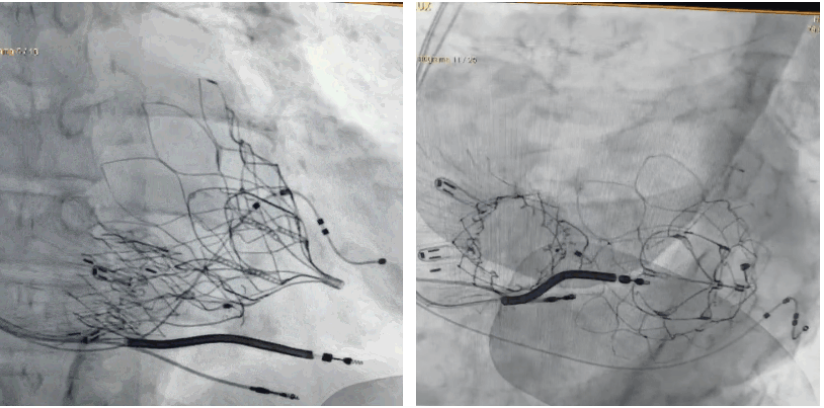

術(shù)后DSA顯示Lux-Valve Plus與Tendyne和ICD無相互影響

手術(shù)在全麻狀態(tài)下進行。術(shù)者采用經(jīng)右側(cè)頸靜脈入路的方式將輸送器送入患者心臟內(nèi),在TEE及DSA引導下調(diào)整輸送器頭端角度,使得輸送器與三尖瓣瓣環(huán)平面垂直。在輸送器進入右心室后釋放室間隔錨定裝置,而后釋放瓣葉夾持件(2個耳片結(jié)構(gòu))成垂直狀態(tài)。在TEE及DSA確定夾持件固定至三尖瓣葉根部且位于右室側(cè)后釋放人工瓣心房側(cè)盤片。隨后調(diào)整瓣膜同軸性以及室間隔錨定件位置(貼合室間隔),前推藏針管并固定,進而釋放室間隔錨定裝置,并再次確認瓣膜位置、穩(wěn)定性及同軸性,合攏輸送鞘后撤出輸送器,完成LuX-Valve Plus人工三尖瓣瓣膜的植入,僅殘余微量瓣周漏。且經(jīng)手術(shù)中心電生理團隊評估,病人的起搏器和ICD功能沒有受到影響。

LuX-Valve Plus經(jīng)血管三尖瓣置換系統(tǒng)此次“出海”圓滿完成,術(shù)后Rodrigo Estévez-Loureiro教授對LuX-Valve Plus經(jīng)血管三尖瓣置換系統(tǒng)的器械性能和治療效果大為稱贊,認為LuX-Valve Plus的手術(shù)體驗非常好。術(shù)后即刻超聲顯示三尖瓣反流幾乎完全消失,血流動力學改善顯著,患者恢復快。在面對復雜解剖結(jié)構(gòu)、超聲影像質(zhì)量不佳、有起搏導線干擾時,Lux-Valve Plus也體現(xiàn)了極強的適應(yīng)性。Thomas Modine教授和Anson Cheung教授也肯定了LuX-Valve Plus術(shù)中操作的便捷性,認為LuX-Valve Plus容錯率高,對術(shù)中影像的依賴較小,后期希望可以更多的應(yīng)用LuX-Valve Plus三尖瓣置換系統(tǒng)于臨床實踐,讓更多的三尖瓣重度反流患者盡早獲益,改善預后。